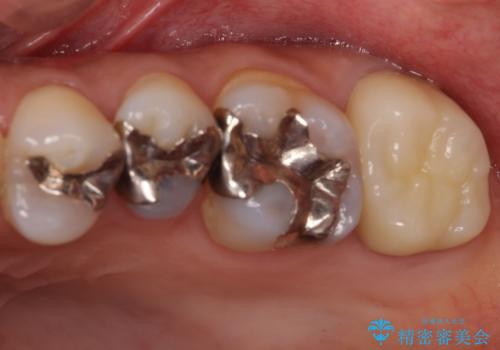

- 上下の奥歯にものが挟まりやすいことを気にして来院された患者様です。

上下ともに、やや大きいむし歯があり、そこにものが挟まりやすくなっていました。

上顎の奥歯は神経にまで虫歯が及んでいる可能性が高かったため、抜髄や断髄の可能性を考慮しながら処置を進め、セラミッククラウンにて補綴することとしました。